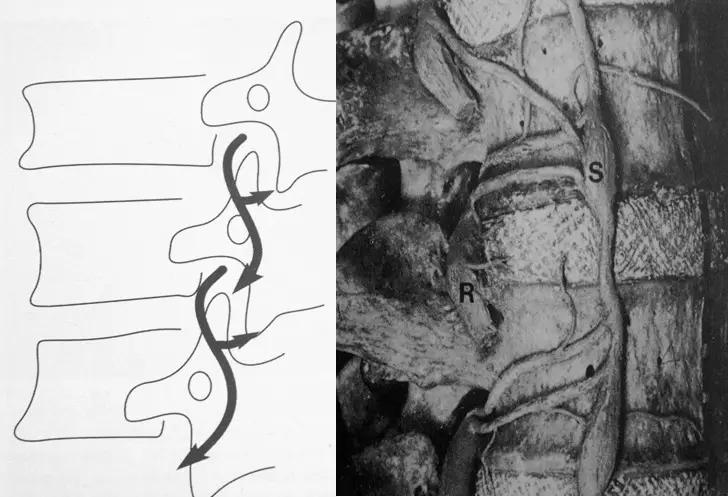

椎间盘与神经根的关系

椎间盘突出的CT表现

直接征象:A、椎间盘后缘向椎管内局限性突出,密度与相应椎间盘一致,形态不一。B、突出的椎间盘可有大小、形态不一的钙化,多与椎间盘相连;C、椎管内硬膜外可见髓核游离碎片,密度高于硬膜囊;D、许莫结节表现为椎体上(下)缘边缘清楚的隐窝状压迹,多位于椎体中后1/3交界部,常上下对称出现。其中心密度低,为突出的髓核及软骨板,外周为反应性骨硬化带。

间接征象:A、硬膜外脂肪间隙变窄、移位、或消失。B、硬膜囊前缘或侧方及神经根受压移位。C、周围骨结构改变,突出髓核周围骨质硬化。

椎间盘突出示意图